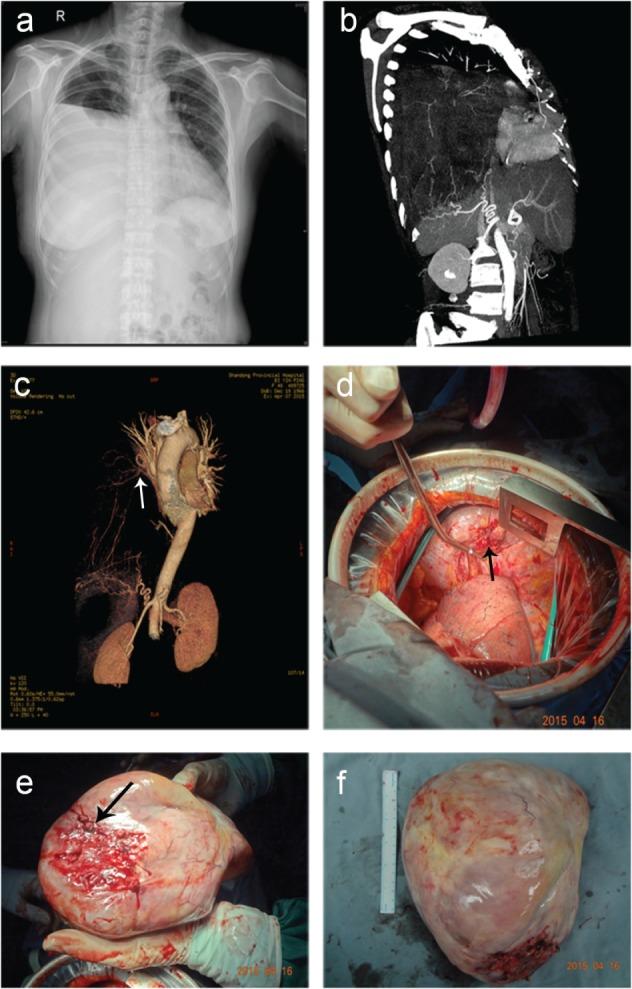

A giant thoracic neoplasm is extremely rare and poorly understood. Our systemic study introduced computed tomography angiography (CTA) with three-dimensional (3D) reconstruction imaging and evaluated correlations between imaging, pathology, and surgical management.

The clinical characteristics, imaging manifestations, and pathological types were complicated. Four patients underwent CTA with 3D reconstruction imaging and feeding vessels were found in three cases. Twenty-four selected patients accepted preoperative biopsy, eight of which were inconsistent with postoperative pathology. Complete resection was performed in 39 cases, 20 of which underwent extended excision. The median survival duration of all patients was 58 months (range 3.0-118.0). The one, three, and five-year survival rates were 86.0%, 64.4%, and 47.0%, respectively. Univariate analyses showed tumor size and resection status were prognostic factors for survival (P = 0.003 and P < 0.001, respectively).

A giant thoracic neoplasm should preferably be treated in experienced centers for precise diagnosis and optimal therapy schemes with comprehensive consideration of clinical characters, imaging manifestations, pathology, surgical management, and prognosis. Innovative CTA with 3D reconstruction imaging together with preoperative biopsy are feasible and effective in therapeutic decision-making and surgical planning. Complete surgical resection remains the mainstay of curative therapy for all resectable tumors.

巨大的胸部肿瘤极其罕见,目前了解甚少。我们的系统研究介绍了计算机断层血管造影(CTA)三维(3D)重建成像,并评估了影像学、病理学和手术管理之间的相关性。

患者的临床特征、影像学表现和病理类型复杂多样。4 例患者接受了 CTA 三维重建成像,其中 3 例发现了供血血管。24 例患者选择了术前活检,其中 8 例与术后病理不符。39 例患者行完全切除术,其中 20 例患者行扩大切除术。所有患者的中位生存时间为 58 个月(范围 3.0-118.0)。患者的 1、3 和 5 年生存率分别为 86.0%、64.4%和 47.0%。单因素分析显示肿瘤大小和切除状态是影响生存的预后因素(P=0.003 和 P<0.001)。

巨大的胸部肿瘤应在有经验的中心进行治疗,以便进行精确诊断和制定最佳治疗方案,综合考虑临床特征、影像学表现、病理学、手术管理和预后。创新的 CTA 三维重建成像与术前活检相结合,在治疗决策和手术规划方面是可行和有效的。完全手术切除仍然是所有可切除肿瘤的主要治疗方法。